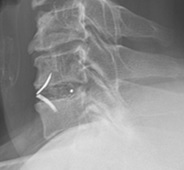

頚椎前方固定術/頚椎後方拡大術:頚椎椎間板ヘルニアや頚椎症性脊髄症に対して、神経の圧迫部位を除去や神経の通り道を広げ、インプラントや自分の骨を移植して固定することで、神経の除圧と症状の改善を目指します。